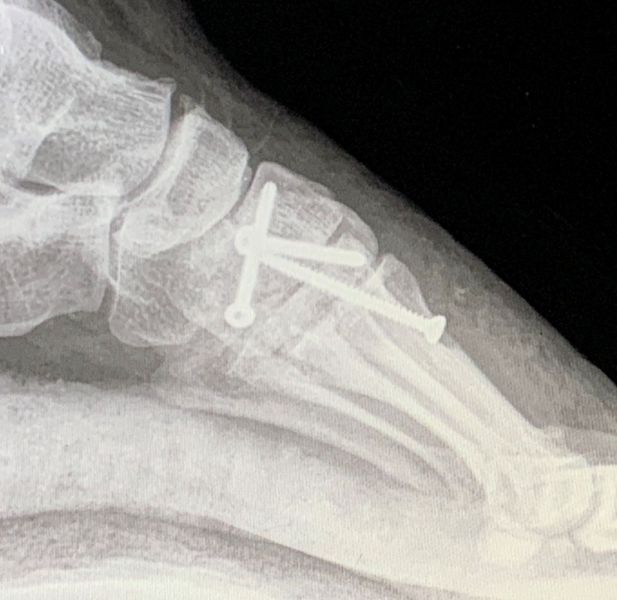

5. Fracture of the left tarsometatarsal joint in a 33-year-old male.

Treatment: Open reduction internal fixation

I. Before surgery, 3D reconstruction of CT scan indicates the Lisfranc injury II. Post-surgery, anteroposterior view of foot with the metal work III. Post-surgery, lateral view of foot with the metal work